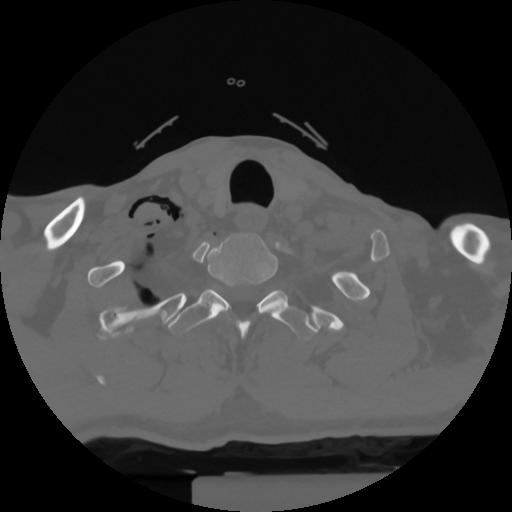

12 P.BLANDAS,,Vol,0.5,P.BLANDAS,,